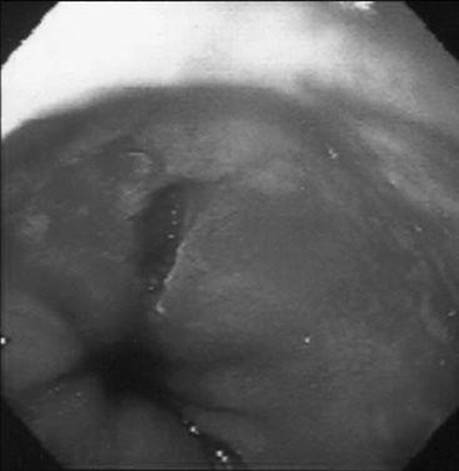

A 35-year-old man presents with massive hematemesis and anemia following an episode of protracted retching. What does the figure show?

Figure 1-2 See also color plate.

Mallory–Weiss tear.